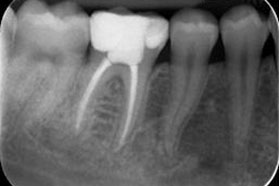

La endodoncia es un tratamiento necesario cuando la pulpa, comúnmente conocida como nervio, se inflama o se infecta. Existen varias causas de infección o inflamación: caries profundas, traumatismos o fracturas. Si no se realiza una endodoncia a tiempo, el nervio puede producir un dolor muy intenso e incluso una infección severa de los tejidos que rodean el diente.

Esta técnica consiste en eliminar la pulpa, limpiar y preparar el interior del diente, para finalmente sellar ese espacio de forma tridimensional.